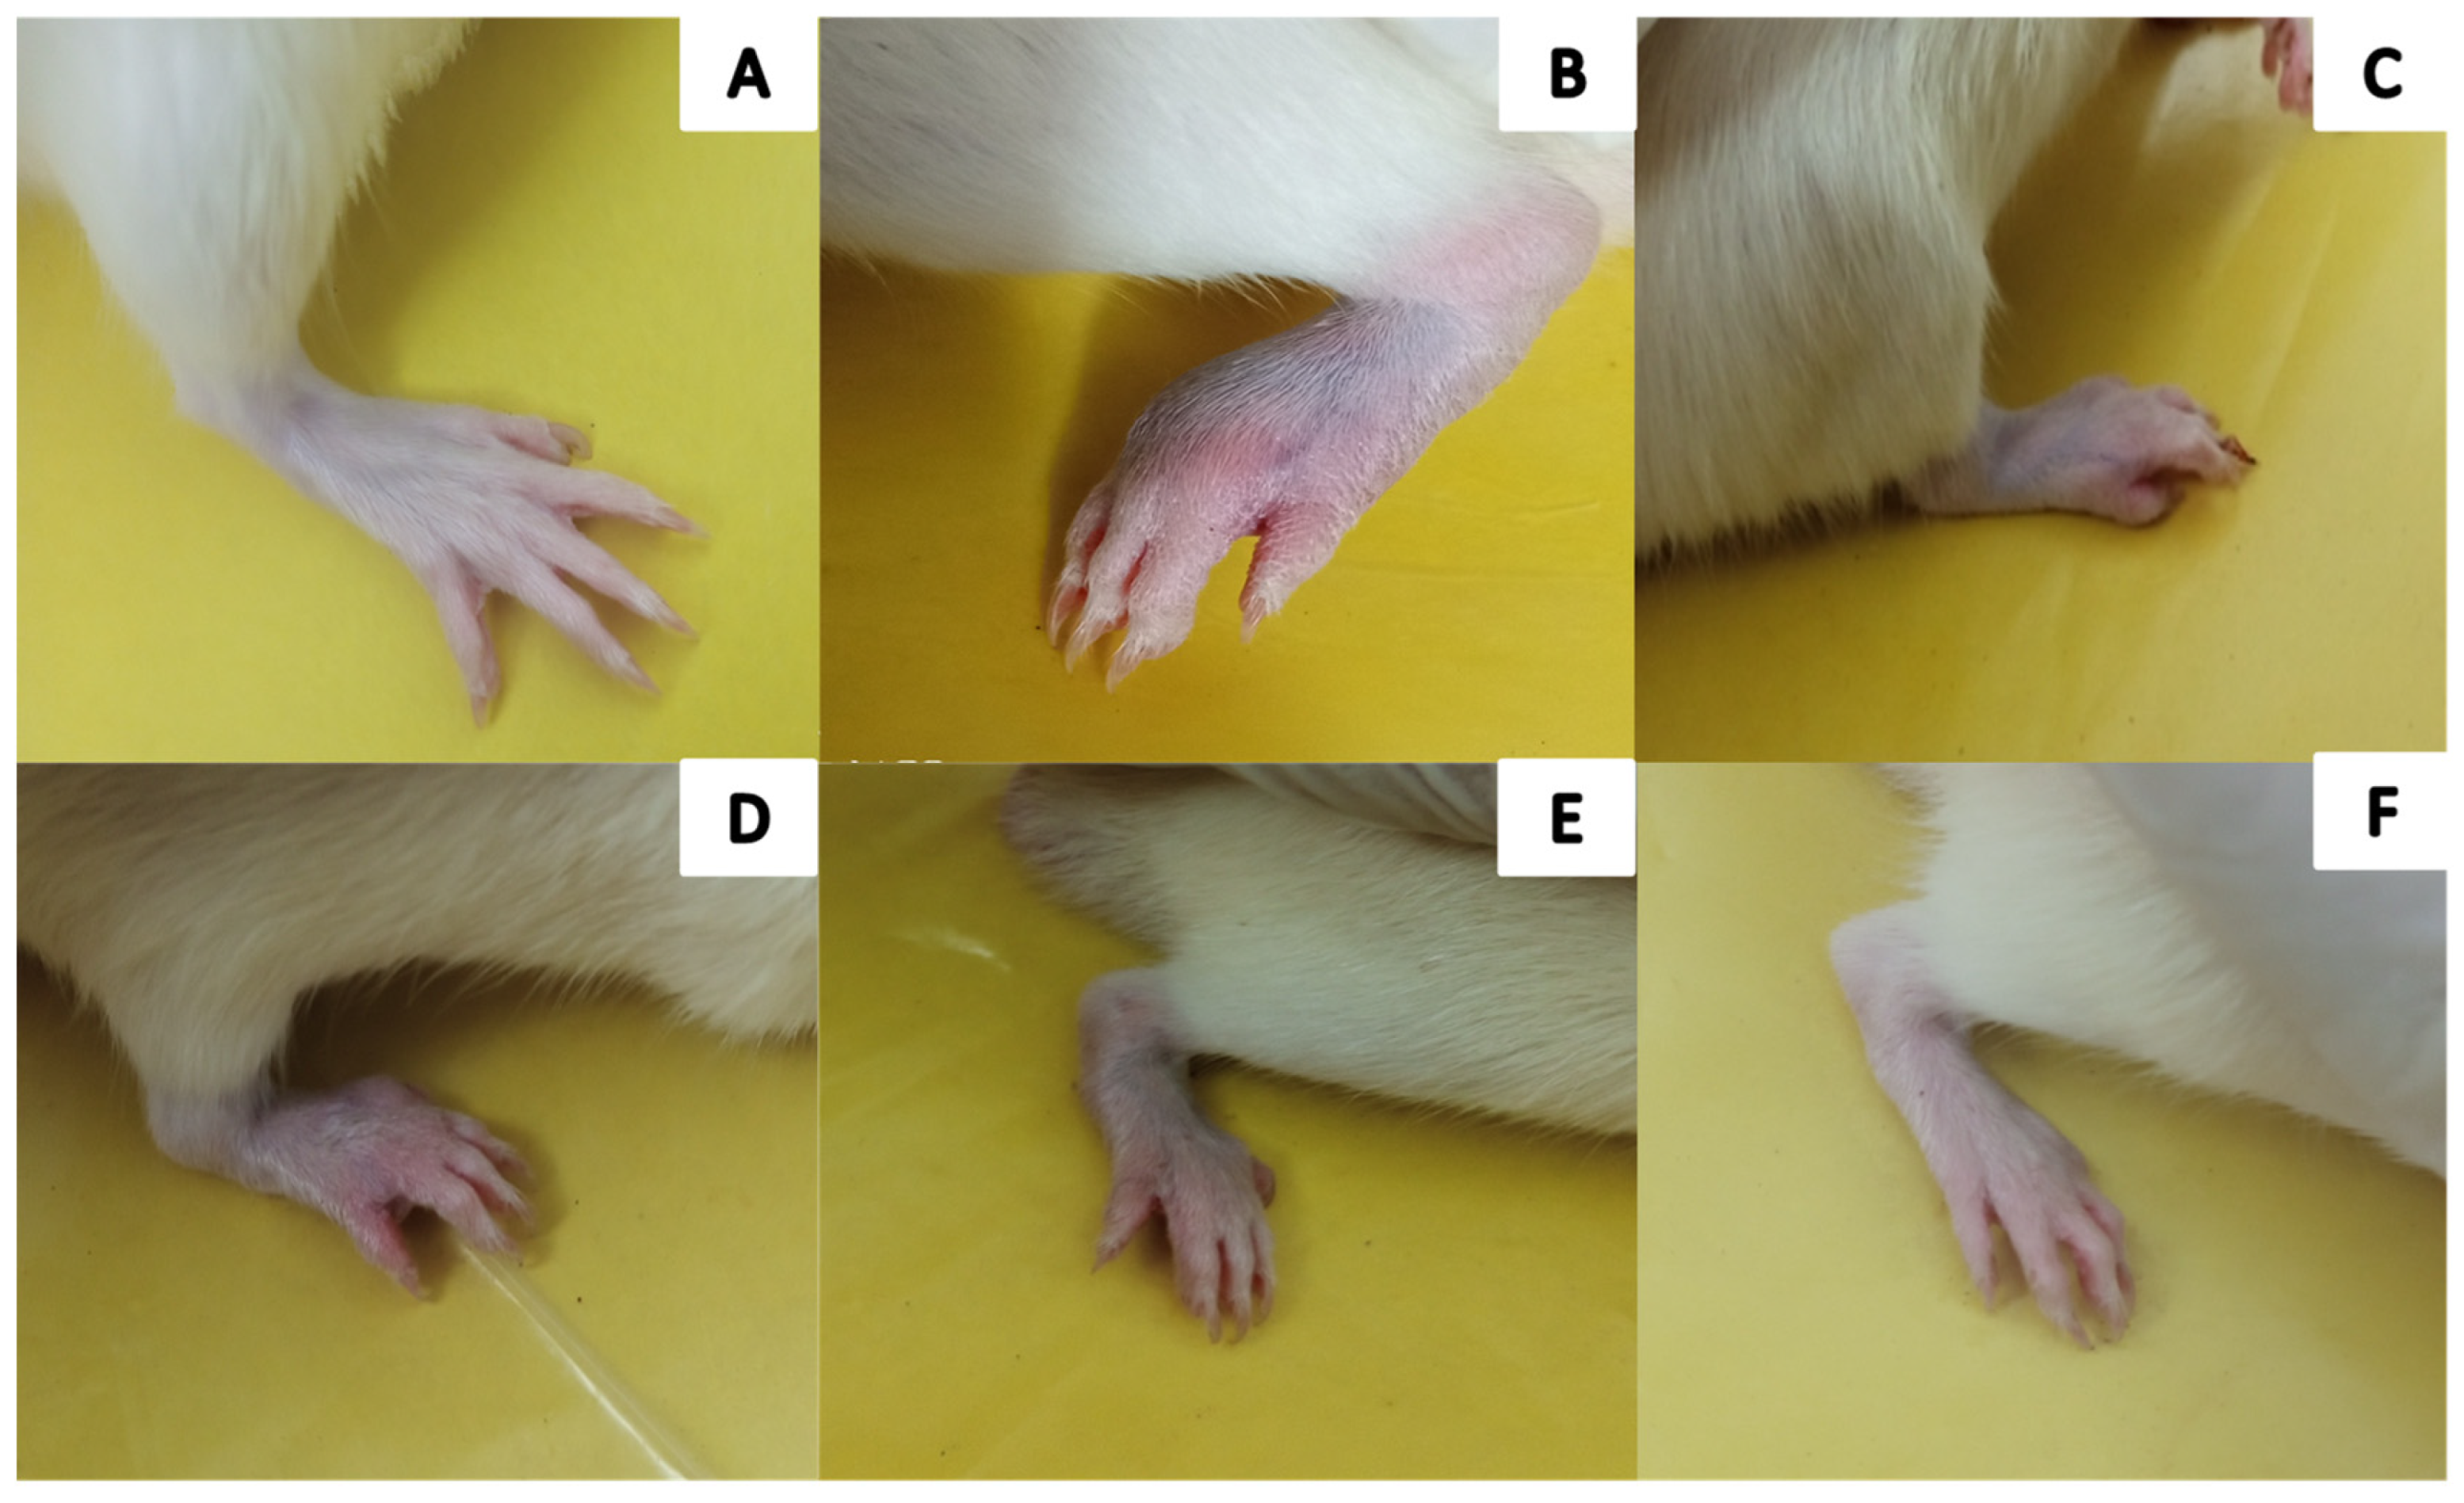

2.6.1. The Visual Arthritic Scoring System

4.7.7. Hot Plate/Thermal Hyperalgesia